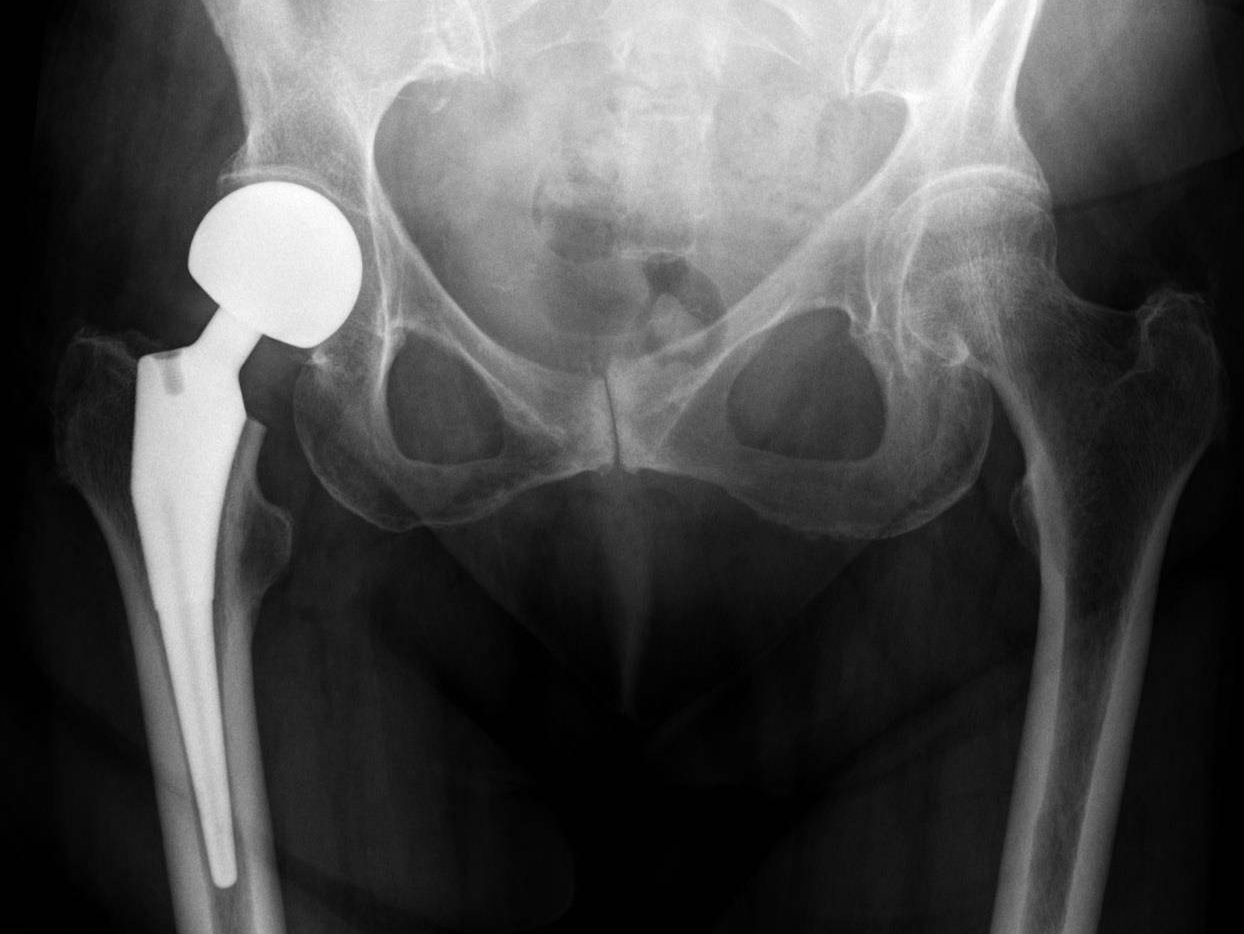

Пятно на шейке бедра - фото презентация